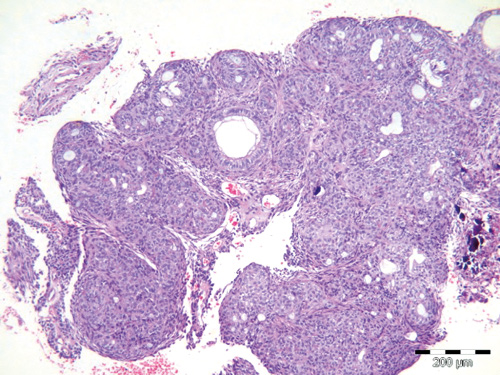

Histologisk er AOT en cellerik tumor med kjertel-lignende strukturer, hvilket har gitt svulsten sitt navn (figur 1 og 2). Der er kubiske celler som er organisert som utførselsganger og små rosetter som kan minne om kjertel-elementer. Gangstrukturene har kubiske celler med kjernen polarisert bort fra lumen. Tumor er omgitt av et modent og løsmasket bindevev, og der er rikelig med blodkar. I mange tilfeller er det henfall av vev, slik at man får inntrykk av cysteutvikling.

Figur 1. Kasus 3: Histologisk bilde av adenomatoid odontogen tumor som viser cellerikt tumorvev som kan minne om kjertelvev med gangstrukturer og celler som er anordnet i rosetter. Målestav: 200 m.